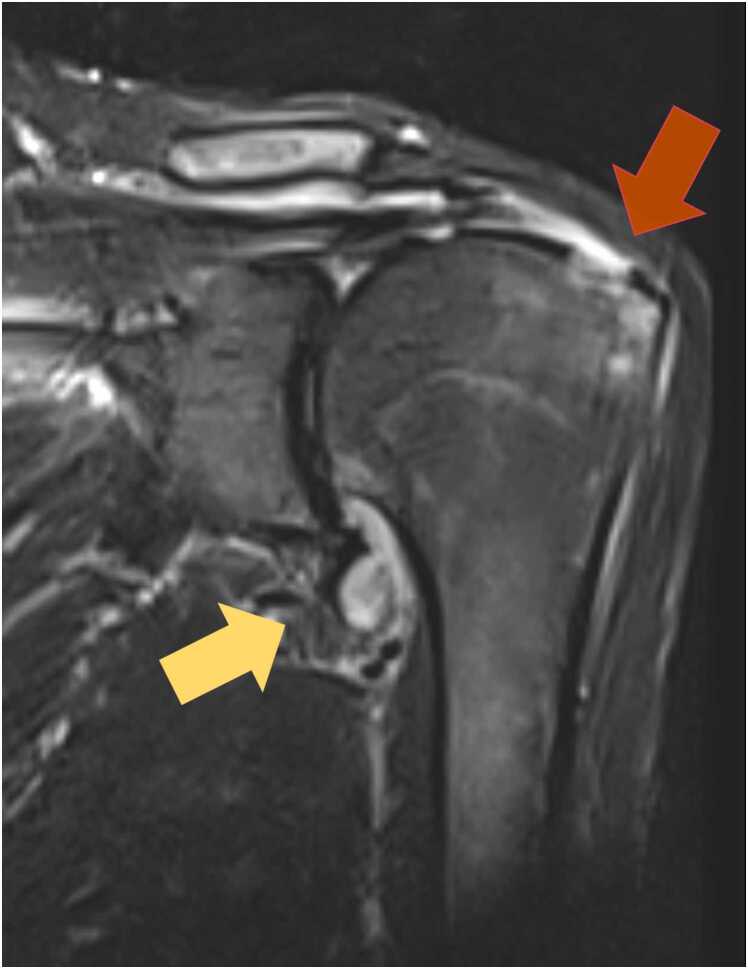

Scrub typhus (tsutsugamushi disease) is an acute febrile illness caused by Orientia tsutsugamushi, often found in Asia and Oceania. The presence of an eschar, characterized by a crust, is a key diagnostic finding. Many symptoms of this disease are already known, however reactive arthritis following scrub typhus is very rare. Here, we present a case of 79-year-old man who was referred to our hospital because of continuous fever and left shoulder pain. We found 4-fold rise in Orientia tsutugamushi-specific IgG titer using paired serum samples and Orientia sp. genes by real-time PCR from a crust of right thigh. And the left shoulder joint image was consistent with aseptic arthritis; thus we diagnosed as scrub typhus with reactive arthritis. This case highlights the importance of recognizing reactive arthritis as a symptom of scrub typhus. In this report, we also review published cases of reactive arthritis associated with scrub typhus, and we suppose that this arthritis related to this infection may recover after antibiotic use and have a good prognosis. Physicians' awareness of newly appeared arthritis may contribute to facilitate early diagnosis, and may improve the course of such patients.